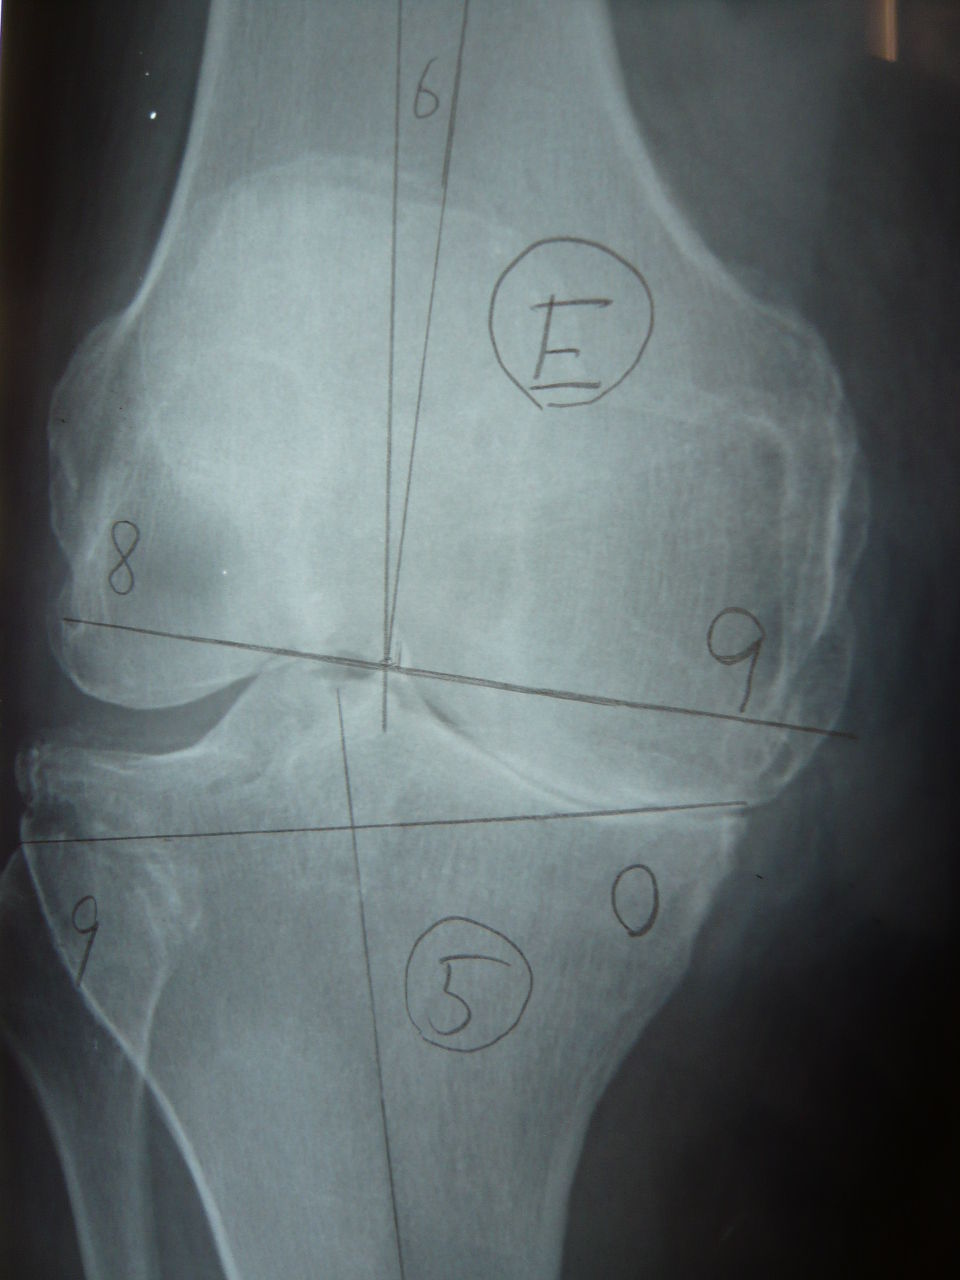

下の画像のように上腕骨顆部が粉砕しており、高度の不安定性をきたしています。

術中所見では、上腕骨小頭は完全にフリーの状態でした。さて、このような骨粗鬆症がベースの上腕骨顆部骨折に対してはロッキングのdual plateによる強固な内固定が必要です。

上腕骨通顆骨折や上腕骨顆部骨折などの遠位骨片が小さい症例では、術前にテンプレートでロッキングスクリューが顆部のどの位置に刺入されるかをシュミレーションする必要があります。

これを怠ると、ロッキングスクリューを顆部の至適位置に刺入できずに固定性不良となる可能性があります。必ず、術前にロッキングスクリューがどの位置に刺入されるのかを確認しましょう。